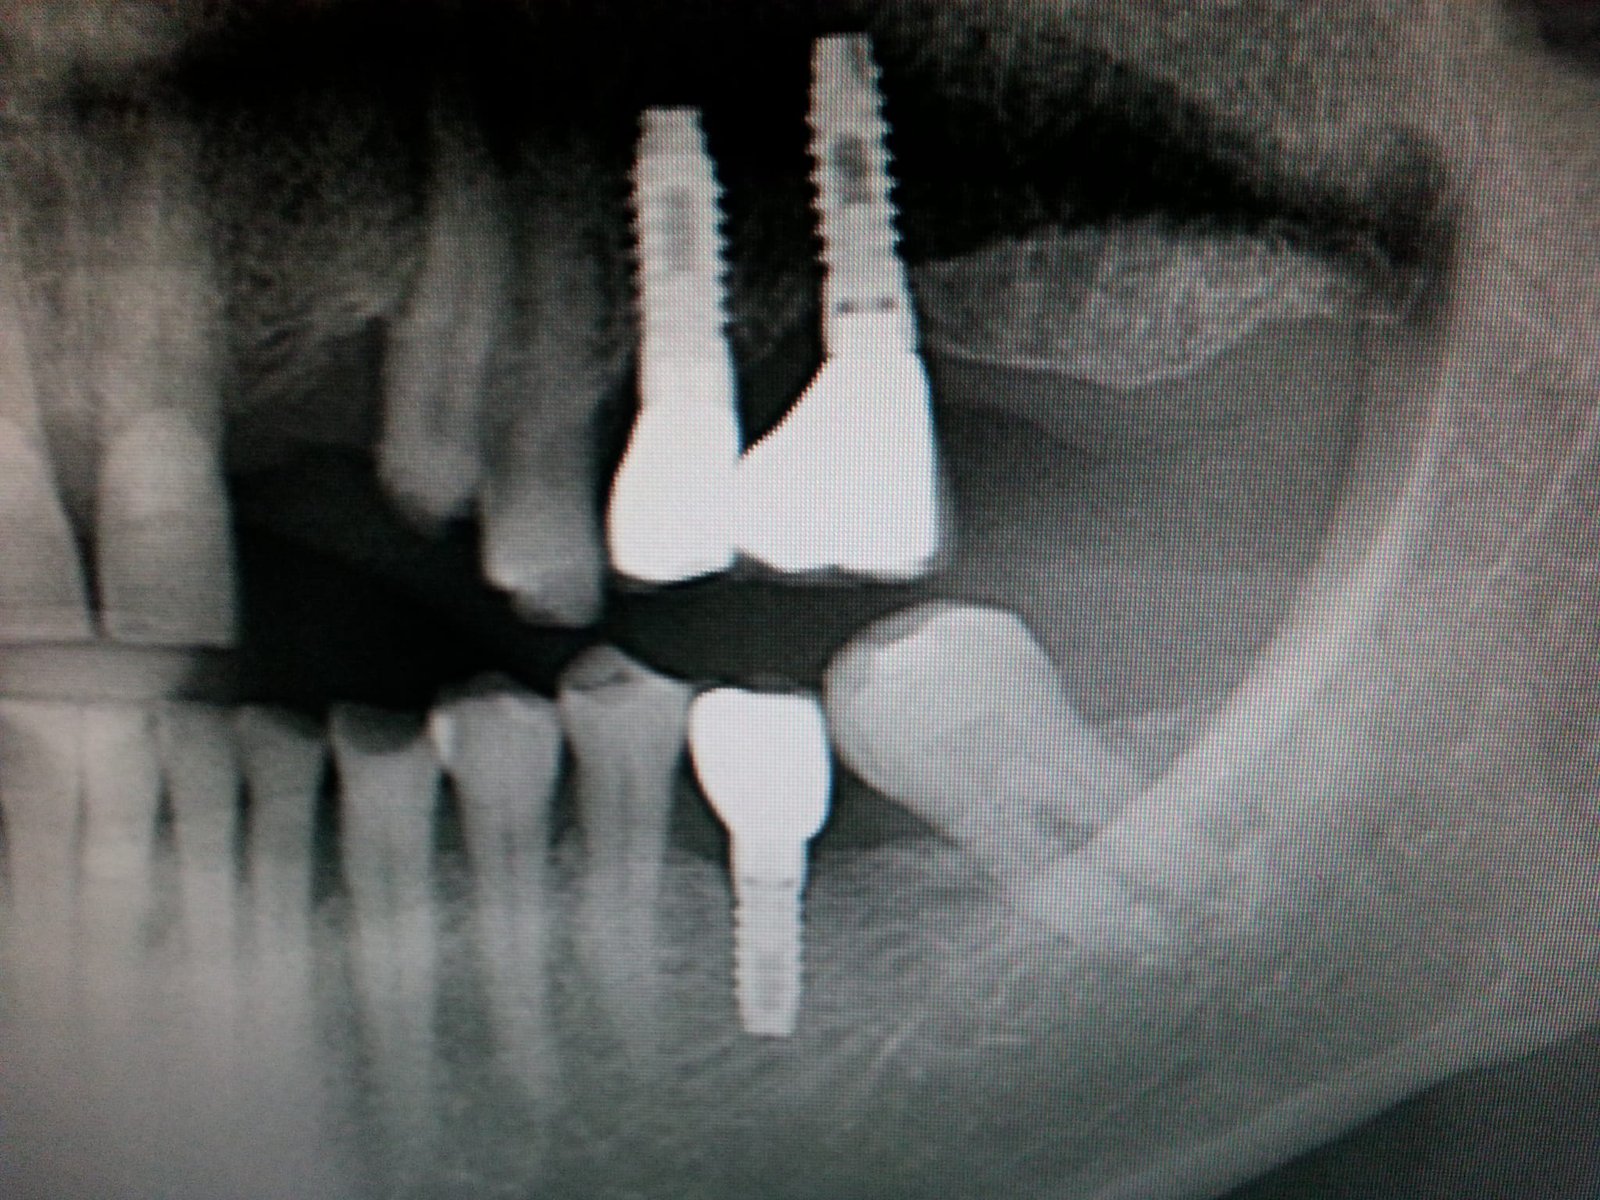

Implantes superiores

Buenos días, quería saber la marca de los implantes superiores. Gracias.